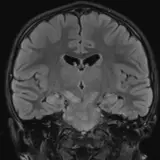

Over 2,100 interactive radiology cases, curated by radiologists for your level of training. Scroll, window, and view cases full screen — just like on PACS. Click linked findings in each writeup to jump straight to them on the image. Cases include sample reports, a focused discussion section, original illustrations, and videos.

Casos totalmente interativos com as ferramentas que você espera em um PACS — rolagem, ajuste de janela, zoom, movimentação, medidas, ROIs e modo de tela cheia.

Anotações detalhadas destacam os achados principais diretamente nos casos. Clique nos achados vinculados nas descrições dos casos para ir ao local exato no exame.

Casos Interativos

Role, movimente, ajuste janela e amplie como em uma estação PACS do trabalho